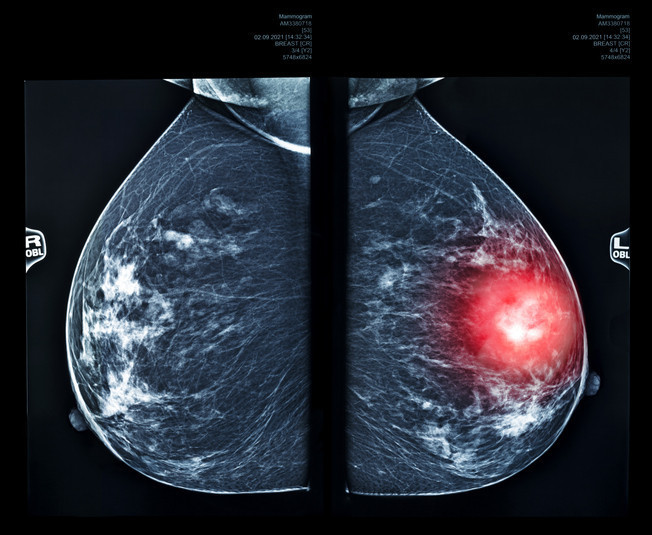

Meme kanseri, memede başlayan bir kanser türüdür. Hastalığın ciddiyeti kanserin boyutuna, yayılıp yayılmadığına ve genel sağlık durumunuza bağlıdır.

Meme taraması (mamografi), elle hissedilemeyecek veya gözle görülemeyecek kadar küçük kanserleri tespit edebilir, bu da tedavinin başarılı olma ihtimalini artırır. Bazen meme kanseri vücudun başka bir bölgesine yayılabilir; buna ikincil (sekonder) meme kanseri denir.